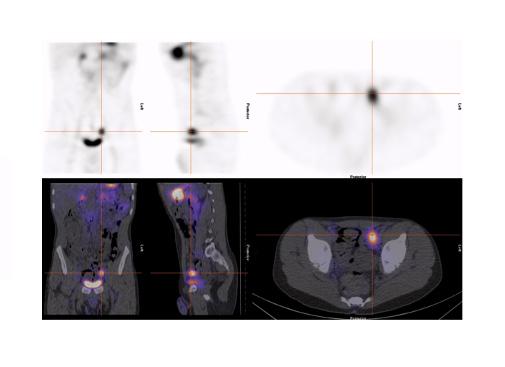

Figure 2 : Étude aux globules rouges avec marquage in vitro (UltratagTM) chez adolescente avec saignement occulte entrainant une anémie sévère. Acquisition dynamique ( A ) et rendu 3D de l’acquisition tomographique (B). Scintigraphie de Meckel sans interférence effectuée 12 jours plus tard. Acquisition dynamique ( C ) et rendu 3D de l’acquisition tomographique ( D ). Les deux études se sont avérées négatives et malgré une investigation extensive, la source du saignement n’a pas été identifié.

Figure 4 : Patient de 13 ans. Rectorragies avec chute de l’hémoglobine. Administration de Zantac IV deux heures avant la scintigraphie. Mise en évidence d’élution au niveau du duodénum et du grêle mais également d’un diverticule de Meckel au flanc droit, près du rein, mieux identifié sur l’étude tomographique. Étude dynamique ( A ) et statique (B) en incidence antérieure, rendu 3D du SPECT (C) et image de fusion (D).